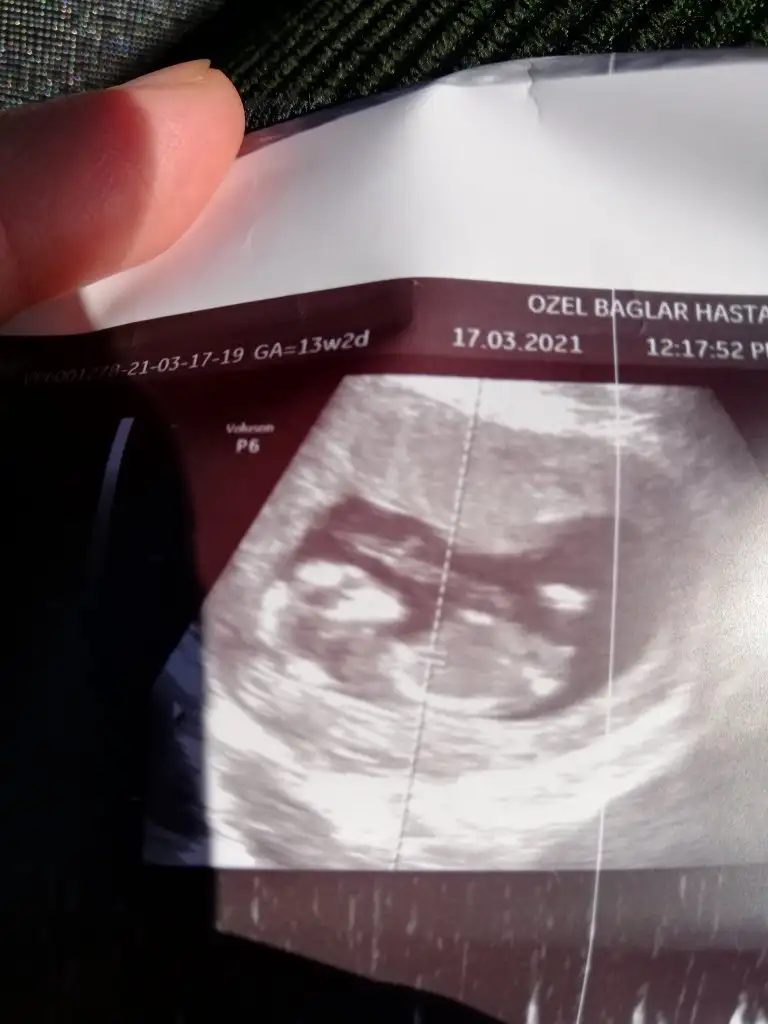

Kızlar 11+5 haftalık cinsiyet tahmini yapabilen var mı 🤩🙏🏻

• IMG_20210318_162633.webp

IMG_20210318_162633.webp

50,6 KB · Görüntüleme: 110